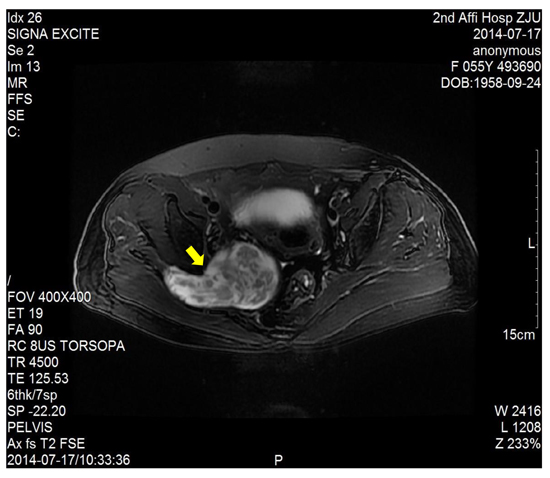

The dimension of the tumors was also shown in Table 1. Lumbosacral CT of our cases were characterized by expansive lesions located in high-sacra such as sacrum 1 and 2, mass appearance on the lateral caudal, well-circumscribed lesions with marginal sclerosis, and the overall benign presentation (Figure 1). In our study, the typical findings of sacral schwannomas in MRI were a well-circumscribed lesion with a heterogenous signal intensity on T2-weighted image. On T2-weighted image, low signal intensity was mixed on the basis of high signal intensity, which was found in our all cases (Figure 2). On T1-weighted image, slightly high signal intensity was mixed on the basis of low signal intensity, which was shown in two cases (Figure 3). Low signal on T1-weighted image was shown in eight patients (Figure 4). T1-weighted images of all cases are characterized by heterogenous enhancement (Figure 5). Average blood loss during surgery was 980ml (ranging between 100 and 2,000ml). Seven patients had only posterior approach as their tumors were limited to the sacrum; two patients went through both anterior and posterior interventions as their tumors extended to the anterior and posterior bone limits of the sacrum; one had just anterior intervention because the tumor was localized to the presacral region. All patients underwent an intralesional resection (piecemeal subtotal excision or shaving) to identify and preserve sacral nerve roots as much as possible. All patients were performed histological examinations after surgery to confirm the diagnosis of sacral schwannomas. Two patients had postoperative bowel and bladder dysfunction after surgery. But they gradually recovered after four months and three weeks, respectively. One patient had cerebrospinal fluid leakage and secondary intracranial infection. This patient finally recovered after several lumbar drainage and anti-infection treatment. All patients were ambulatory postoperatively.

Figure 2: T2-weighted image showed a right sacral mass as a dumbbell-shaped configuration and mixed low signal intensity on the basis of high signal intensity.